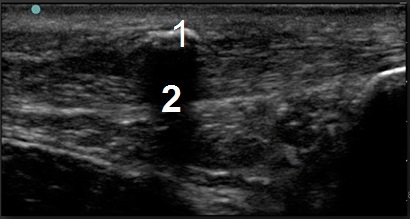

Bild: Fuß und Sprunggelenk, intrasubstantielle Kalkablagerungen

1. Kalziumablagerung innerhalb der Sehne

2. Schatten einer Kalkablagerung (posteriorer Schallschatten)